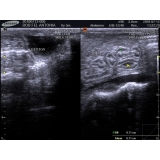

- Ultrassom com hora marcada;